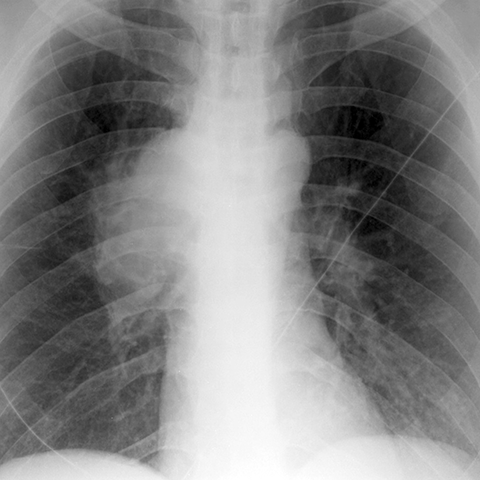

Hilar Nodes in Lung Cancer [1 of 3]